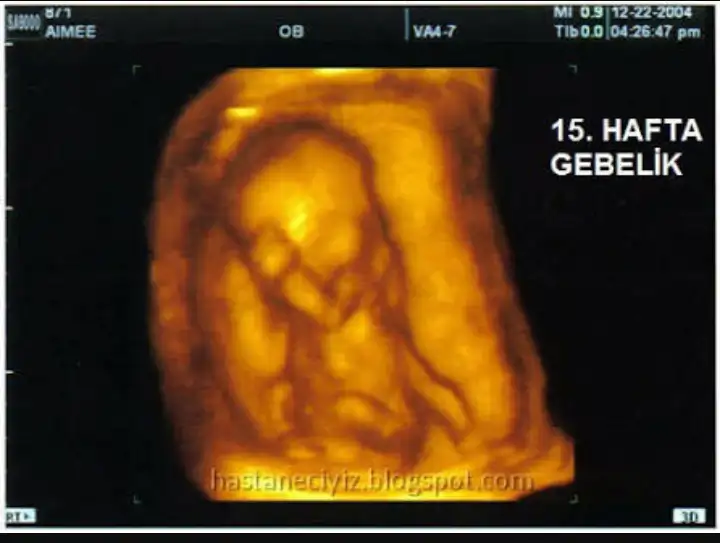

15 haftalik mi? Zaten aldirma olmaz bu durumda yani nasi olabilir ki doktor...

Ama konu sahibi bebek ne demek, nasil olur bilmiyor , hafta hafta nasil gelişir bilmiyor madem sonu böyle olacaktı neden aldirmadi evlenmek neydi ki bu durumda , yani ilk basta bir öyle bir boyle konuşan bir adam var bunlari gormedi mi gün be gün geçirdi günleri bekar hamilelik bebek buyutmekte kolay degil anlayabiliyorum ama bu durumda yapılacak sey 15 haftalık bebeği aldirmak değil yani ne diyeceğimi bilmiyorum... yasal sure 8 hafta mi ?

Ben hamileyken doktor ariyordum ünlü bir proftu haberlerde gördüm eski bir haberdi ikiz bebege hamile kadin, çocuklarin biri down sendromlu ailenin demesine gore kadini ikna ediyor ikizlerden birinin kalbini iğneyle durduruyor bu yani anne karnından içeri iğneyle kalbini durdurup doğum yaptırıyor.. sonra annede ölmüş dava açılmış... 15 haftalik ise bu bebek dedikleri seyi yaparlarsa ölü doğum yaptıracaklar... kalbini durdurup suni sanci verilecek dogum olacak herşeyi gorecek konu sahibi kürtajda bayiltiliyor ama bunda doğum yapacak